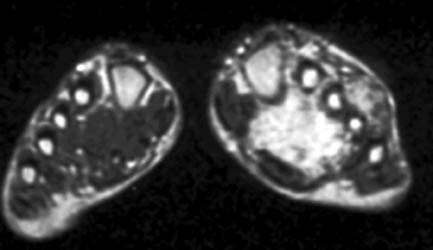

MR findings- Synovial proliferation with synovial fluid demonstrating as inhomogeneous high signal intensity on T2W images. Hemosiderine deposition is seen as low signal intensity foci on T1W and T2W images. Cystic bony erosions are present in fifty percent of patients.

26 years old female presenting with painful soft tissue mass at the plantar aspect of the left foot.MR demonstrates this mass is isointense on T1,isointense to minimally hyperintense on proton density and hyperintense on T2 W and Stir images. Bony erosions are identified in 3rd cuneiform, cuboid and bases of 3rd and 4th metatarsals on MRI and plain radiographs.Few foci of low signal intensity hemosiderine deposits are identified on all pulse sequences.